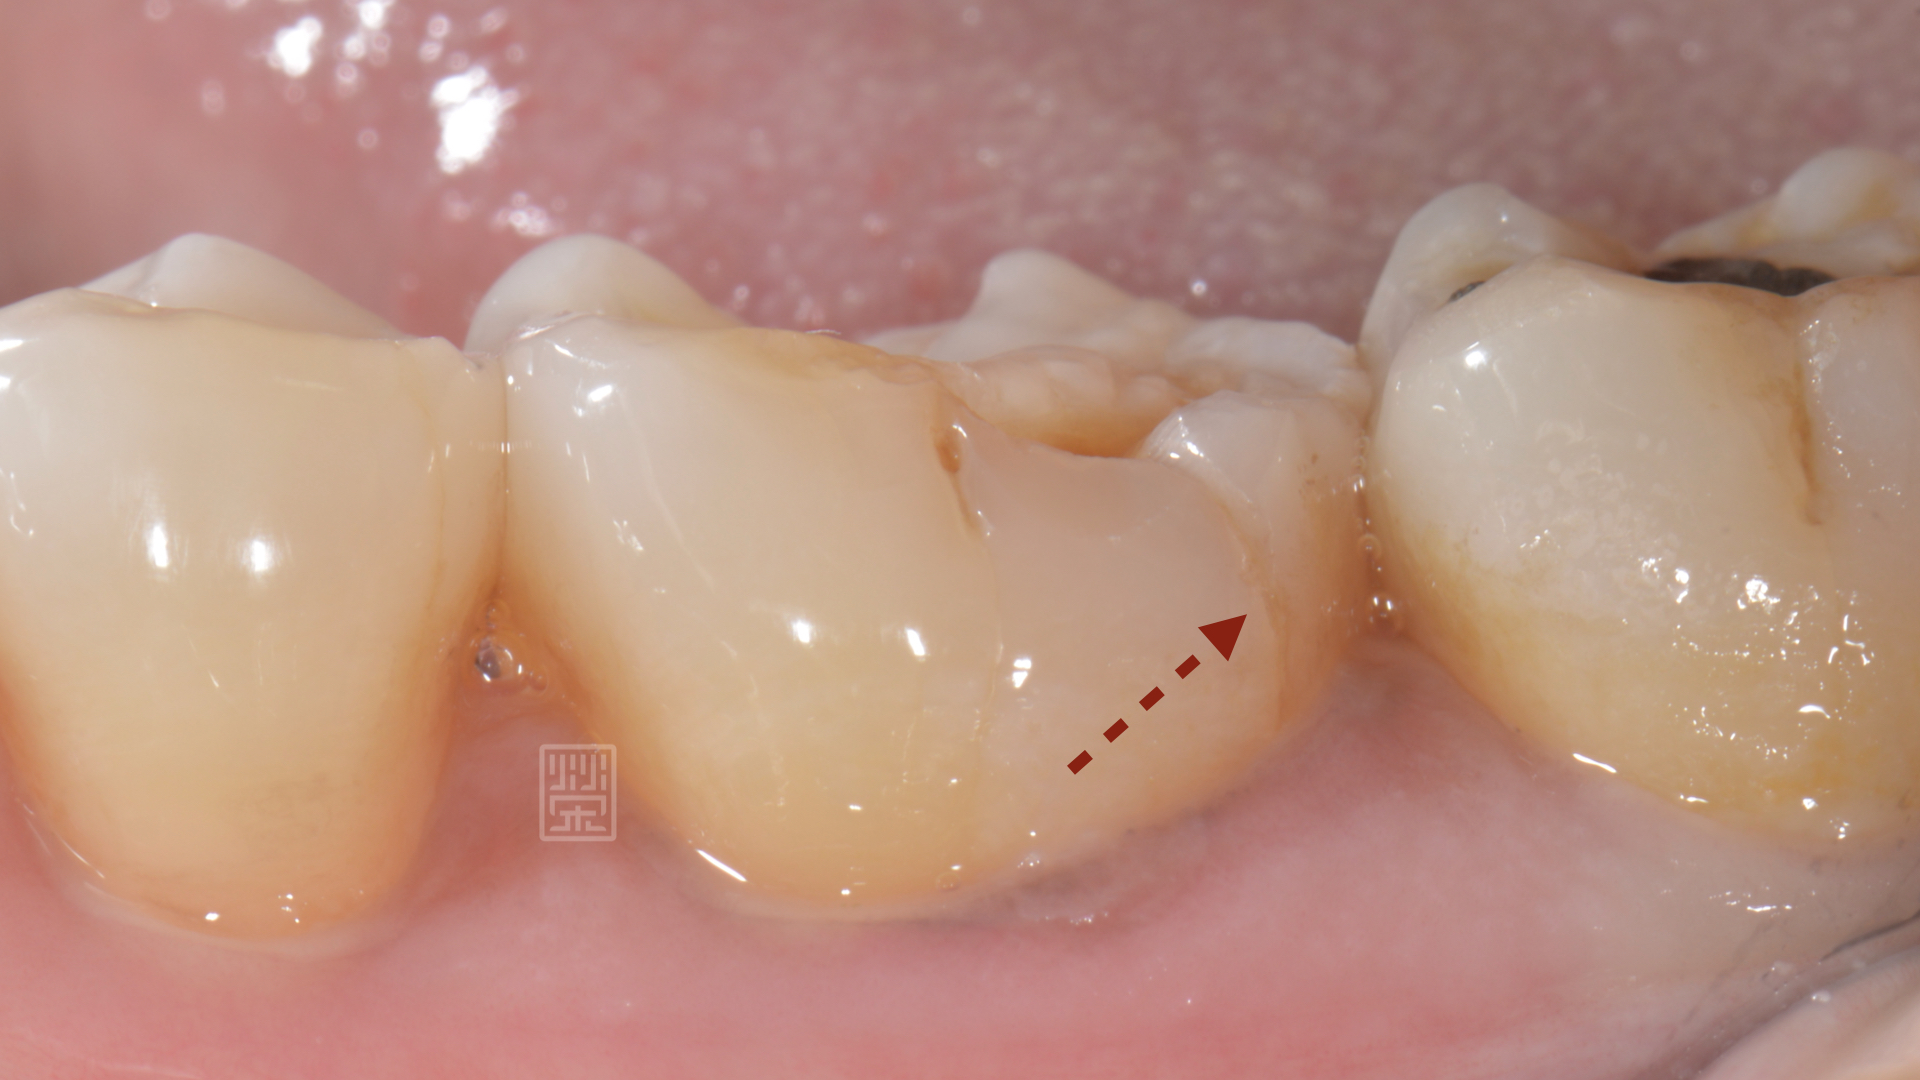

楊女士因為上顎第二大臼齒缺牙,所以咬合重心都是在第一大臼齒咬合對,前陣子突然發覺咬東西有點痛痛的,以為是牙齦發炎,認真刷牙後,狀況並未改善,來榮醫師診間就診,發現除了咬合面明顯磨耗,牙本質都裸露之外,頰側面有明顯的縱向裂痕,還好的是牙齒神經並未造成不可逆傷害,建議製作全瓷嵌體,將牙齒戴上保護罩,減少治療過程牙齒的傷害。

頰側有裂痕